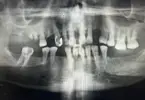

د. إنان أوزتورك طبيب أسنان

طب الأسنان